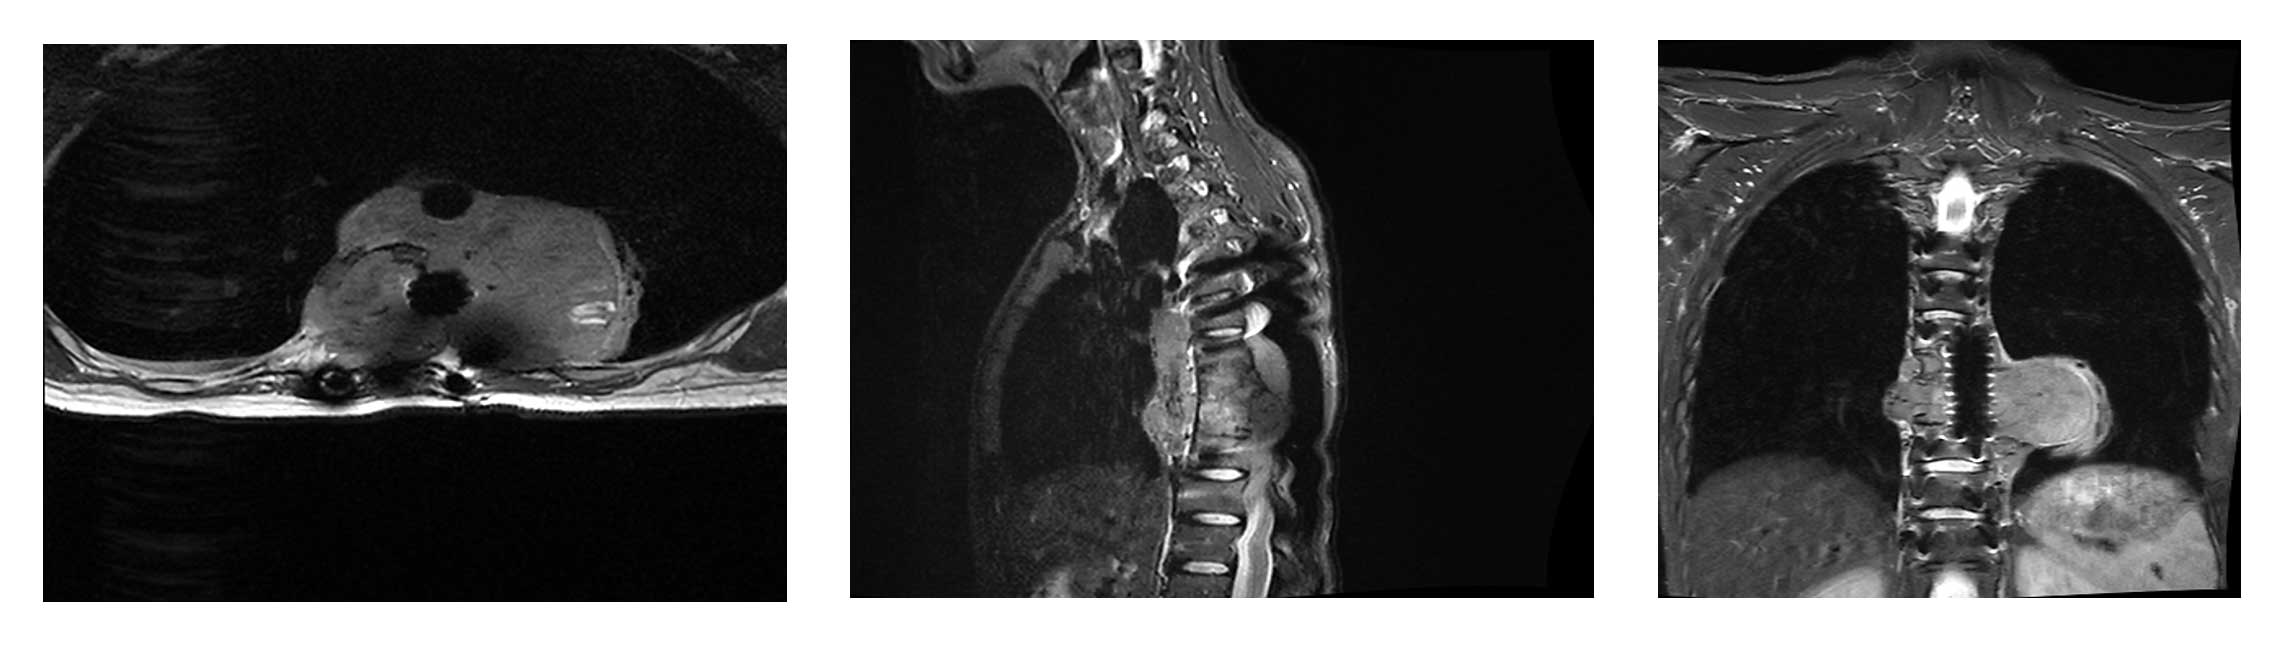

Ameliyat Öncesi: MR’da büyük boyutta tümör nüksü görülmekte.